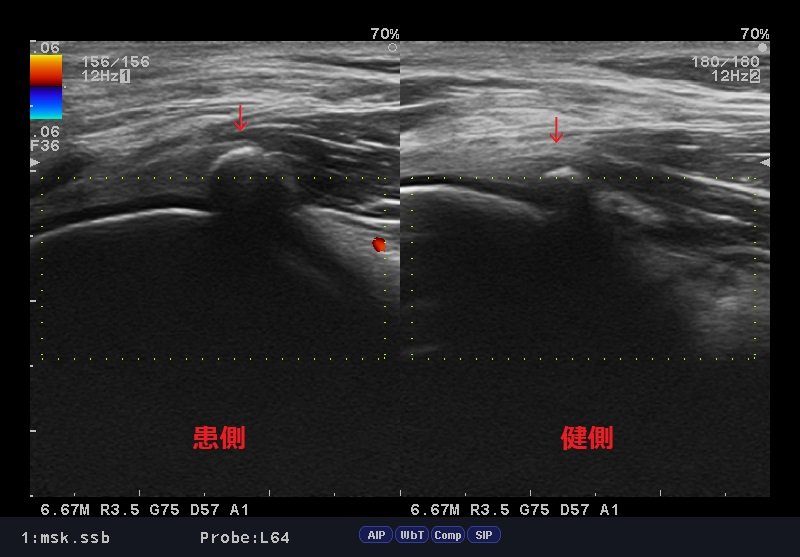

ファベラ症候群エコー.jpg

結果、膝窩ファベラ周囲に炎症反応が診られ「ファベラ症候群」と判明